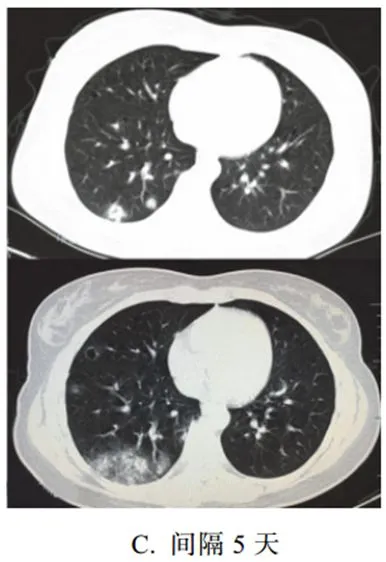

三、重症期征象

新冠肺炎肺部病变一般在发病后 14 天左右达到高峰,少部分病例急剧进展,病变累及双侧全肺,呈白肺征象,其内可见空气支气管征,双侧胸腔可有少量胸腔积液,临床纳入危重症管理

根据既往病理学机制提示肺泡腔有大量纤维素性渗出

3. 重症期表现为大范围肺组织密度增高实变,少数呈白肺征象